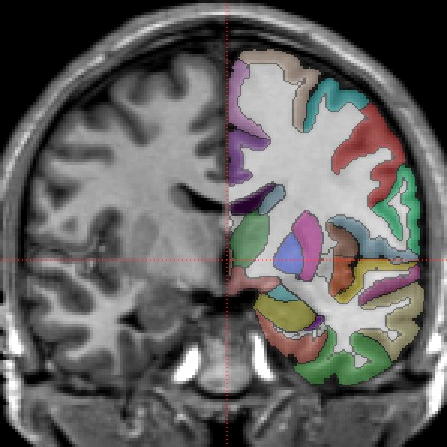

These manually labeled MRI brain scans can be embedded into a medical device or image analysis software where precise neuroanatomical localization is important such as automated brain labeling algorithms, training deep learning, neuroanatomical visualization, and stereotactic radiosurgery, to name a few application areas. Unlike an atlas of a single subject, our database of scans provides an indication of the variation of the living human brain. Currently there are 114 scans with subject ages from 5 to 96 years old.

We have the most comprehensively labeled scans and the

largest number of scans available anywhere. We label the

entire brain and divide the cortex into regions based on gyral and

sulcal landmarks using 1) the “General Segmentation” Protocol

defined by the MGH Center for Morphometric Analysis

(see here), and 2) the brainCOLOR Cortical Parcellation Protocol (from here). The consistency of our